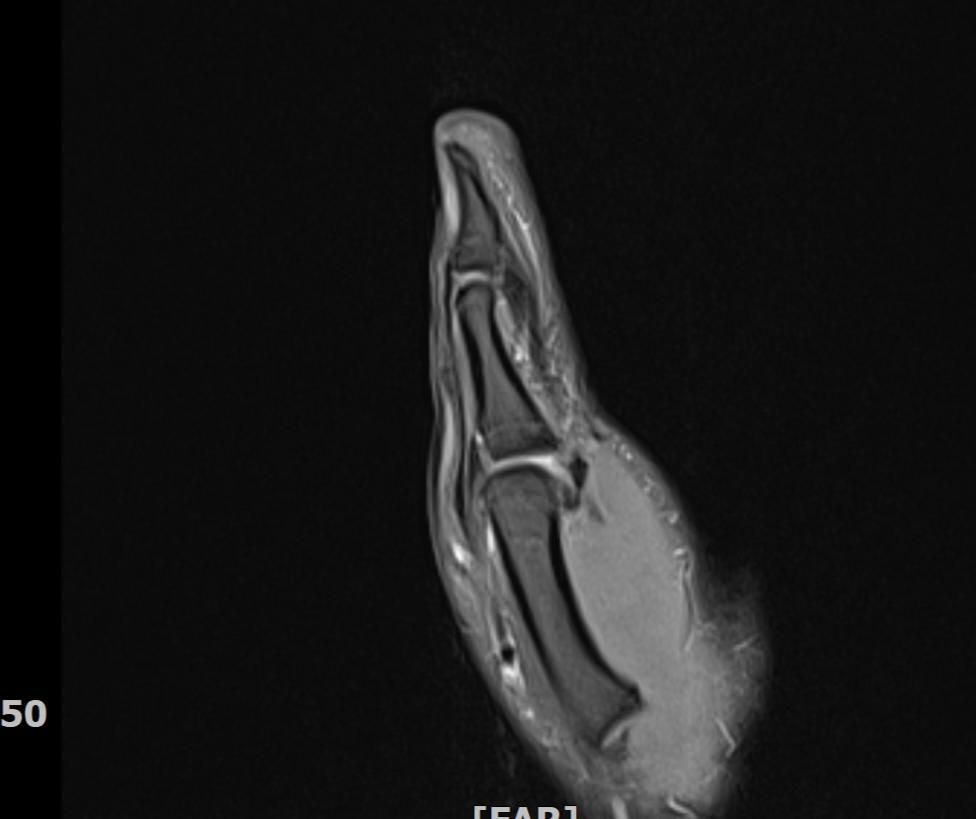

왼손 엄지손가락 부상 mri판독부탁드립니다

임팩에 장갑이 말리면서 엄지도 같이 말렸습니다

현재 손이 가끔 욱씬거리고 평소보다 뻣뻣하며 불안정감이 있는듯 합니다. mri사진으로 판독 가능하실까요 감사합니다.

• 3번 째 사진

정확한 판독을 하긴 어렵지만 연부조직의 주변부의 염증이 보여집니다.

올려주신 사진 상에서는 특별하게 큰 문제가 없을 수 있으나 부상과정에서 인대나 힘줄에 발생했던 부상으로 인해 긴장감이나 움직임 제한, 통증이 나티나는 경우에는 치료를 받아보시는 것도 좋겠습니다.

Mri 판독은 영상 전문의가 직접 이미지를 확인해야 정확하지만 엄지 부상 후 욱씬거림과 뻣뻣함, 불안정감은 인대 손상이나 골절, 건초염 가능성을 시사합니다. Mri에서는 인대 파열, 연골 손상, 골수 부종 등을 중점적으로 평가합니다. 증상이 지속되면 정형외과 전문의에게 영상 판독과 임상 진단을 반드시 받는 것이 안전합니다!